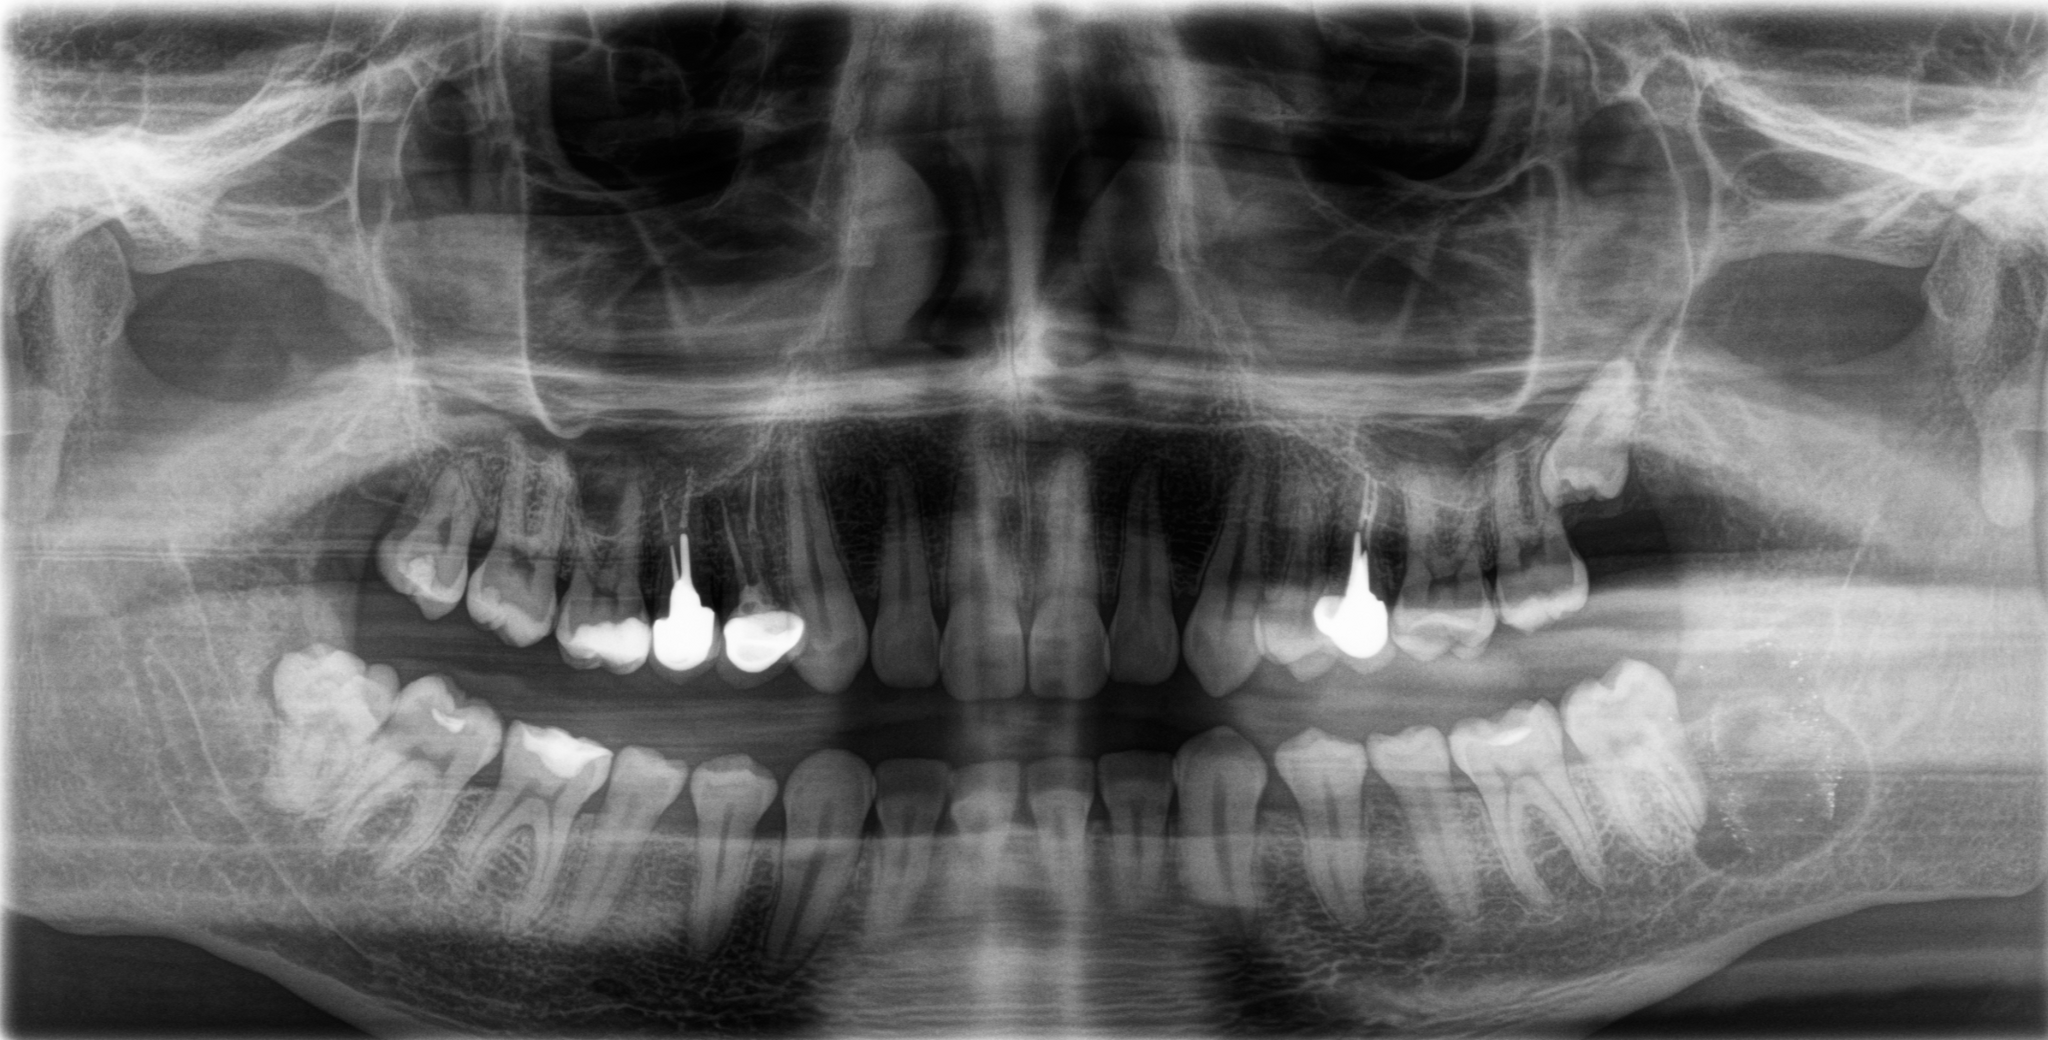

На прием пришла девушка с пожеланием восстановить удаленный ранее в другой клинике зуб на верхней челюсти справа. Ну что ж, без проблем. Направляю пациентку на компьютерную томографию для оценки ситуации. И вдруг я вижу «её» – притаившуюся в пазухе омерзительную восьмерку, которая, противно ухмыляясь, смотрит прямо на меня.

Красным пунктиром отмечено разрастание фолликулярной кисты, которая распространилась в область корней зуба по соседству.

На панорамном снимке, сделанном после имплантации, хорошо видно, насколько высоко и неудачно она располагается: